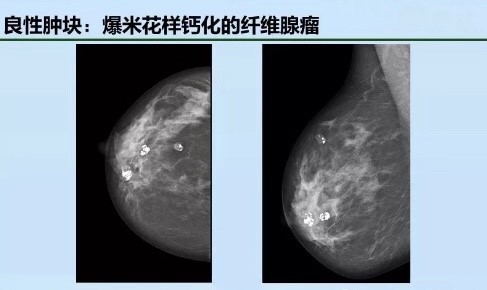

二、发现肿物

在两个不同投照位置均可见到的占位性病变,其中以其边缘征象对判断肿块的性质最为重要,可表现为边缘清晰、模糊、浸润性生长,或可见到从肿块边缘发出的放射状线影。乳腺肿块与其周围乳腺组织相比,多数呈高或等密度,极少数可表现为低密度。